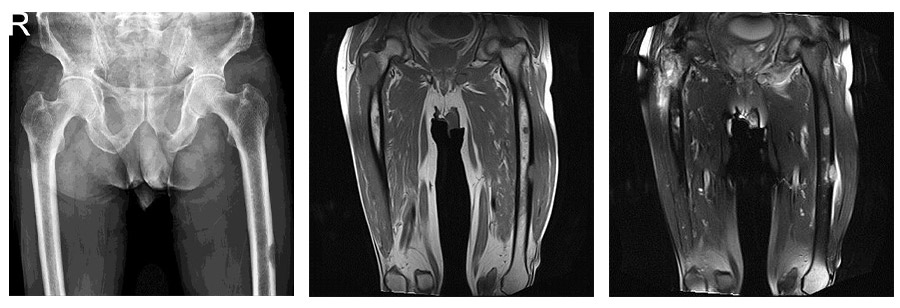

CASE 28: Lung cancer increases the risk of fractures due to metastasis to both femur (thigh bone).

Before the surgery: X-rays and MRIs show metastatic foci in both femur bones that are causing destruction and posing a risk of fracture.